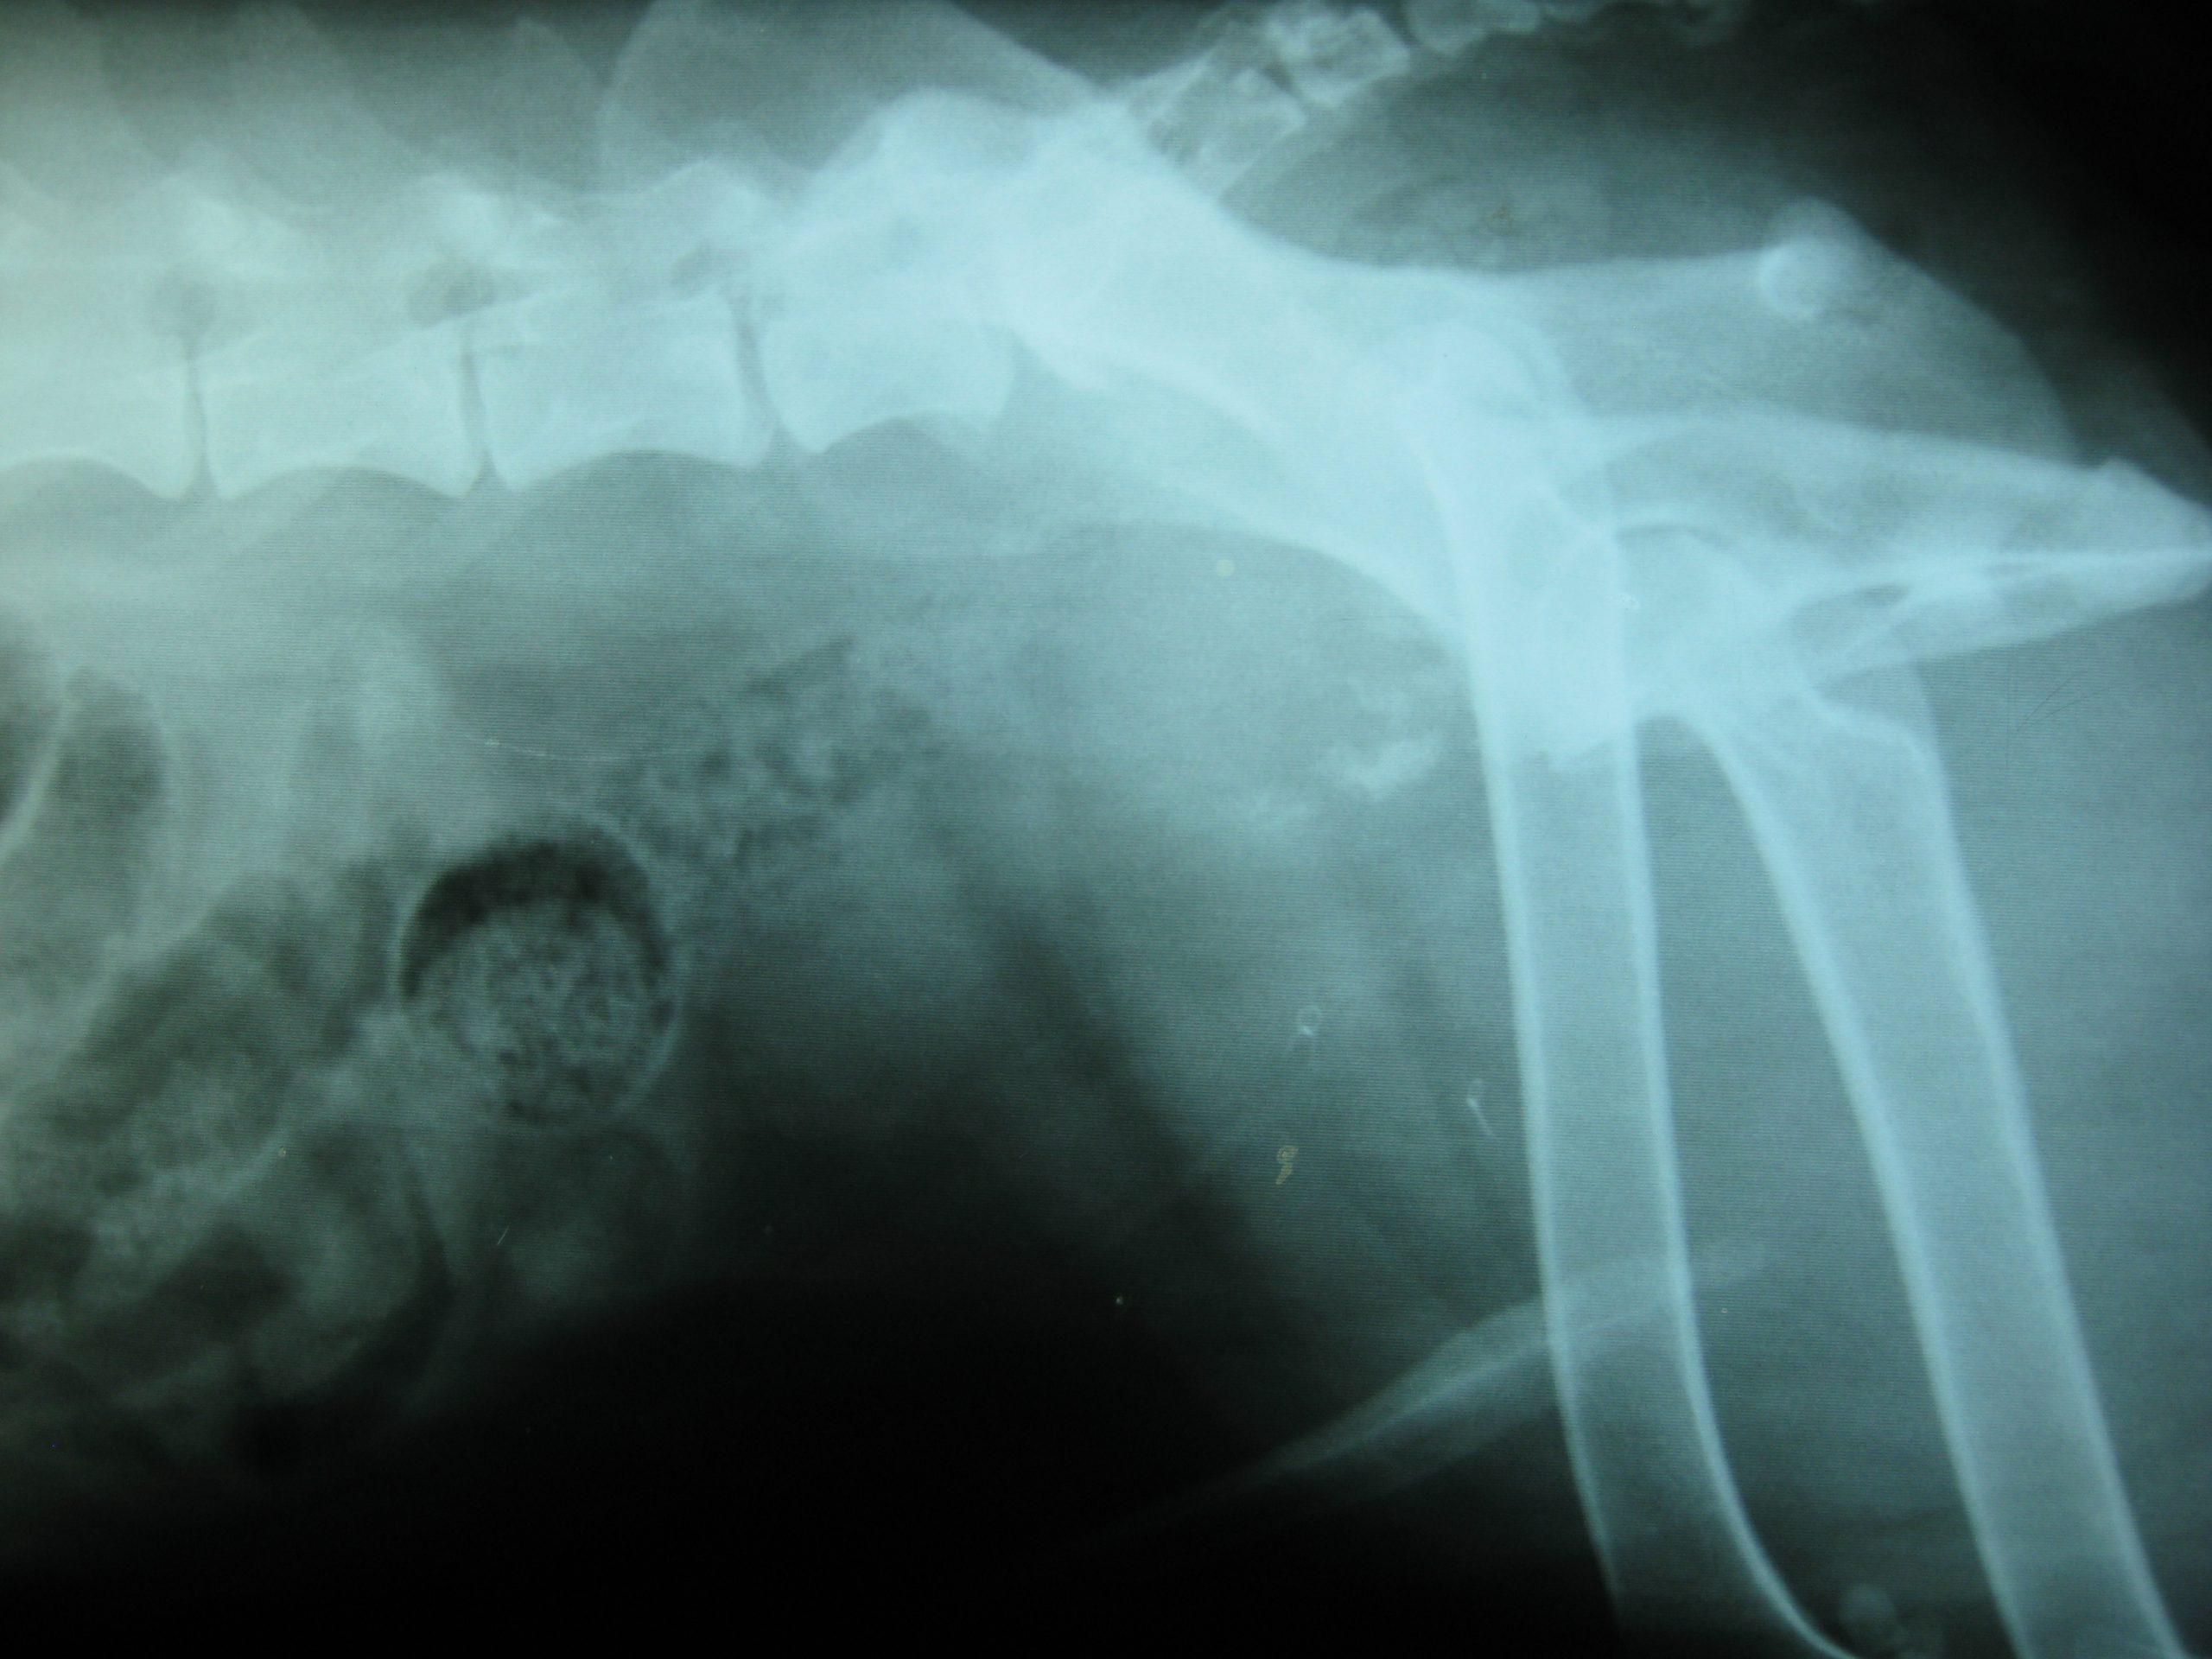

A 9-year-old neutered male Cocker Spaniel dog with a history of chronic diarrhea was presented for evaluation of recent onset hematuria. Prostatomegaly was present on rectal palpation. On survey radiographs, uroliths and narrowing of the distal colon at the pelvic inlet were evident.